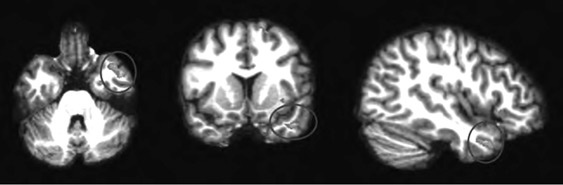

Анализируя далее научную литературу, мы пришли к выводу, что процесс поведенческого подражания с участием верхних отделов височной коры и эмоциональный (физиологический) резонанс, требующий участия островка, тоже имеют отношение к системе зеркальных нейронов. При подражании верхние отделы височной коры кодируют сложные процессы сенсорных следствий двигательных актов; при эмоциональном резонансе островок осуществляет физиологический и аффективный сдвиг, имитирующий его у другого человека. Исходя из параллелизма этих функций реципрокного действия (имитационной, физиологической и аффективной), мы можем использовать термин «резонансный контур», подразумевая, что в нем могут участвовать зеркальные нейроны, но не все компоненты этого контура двигательные, поэтому формально мы не можем назвать такой контур зеркальным. В нашем обсуждении мы примем во внимание это отличие и будем называть резонансный контур именно так, или будем прибегать к выражению «области, связанные с системой зеркальных нейронов» (рис. П.1 и П.2).

П.1

Иллюстрация к книге — Внимательный мозг. Научный взгляд на медитацию [i_014.jpg]

Рис. П.1, П.2. Функциональная МРТ, выполненная во время выполнения медитации осознавания дыхания. На снимках видна активация верхней височной извилины (рис. П.1) и активация островка и вентрального отдела передней поясной извилины (рис. П.2). Верхняя височная кора, островок и области срединной префронтальной коры (показанные здесь) вместе с системой зеркальных нейронов, как предполагается в тексте, содержат элементы «резонансного контура», которые активируются в ходе внимательного осознавания (снимки напечатаны с разрешения Сары Лазар © 2005)